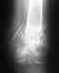

Re: эндопротезирование голеностопного сустава

Alexander Chelnokov 29 Октябрь 2012, 18:35

В нашем инститте делают ндопротезирование голеностопного сустава. Чтобы решить, походит ли эта операция Вам, надо появиться на очную консультацию. Если эта операция в Вашем случае целесообразна, можно будет ее сделать по федеральной программе бесплатно (при наличии направления из местного Минздрава).